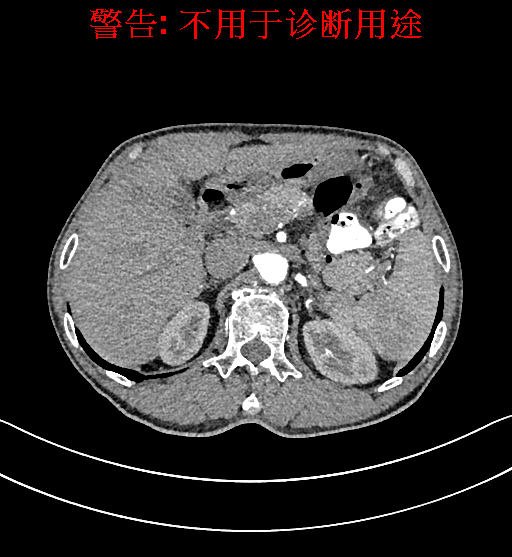

上腹部动态CT扫描示肝左内叶占位,考虑肝Ca可能性大,请结合临床肝多发小囊肿。

将0.625mm双源薄层CT资料的静脉期和动脉期Dicom格式文件导入海信CAS系统。

通过调节窗宽窗位调整CT序号,对肿瘤,肝实质,胆囊,下腔静脉,肿瘤,肝动脉、门静脉及肝静脉等进行三维重建;系统自动计算肿瘤体积和肝脏体积。模拟手术操作,自动计算切除肿瘤体积。肝脏体积为1320ml,肿瘤体积为37.88ml,通过比对70-80岁正常肝脏体积为1263.13±170.25 ml,通过术前模拟手术,精准判断切除后剩余肝脏体积能耐受,避免肝衰竭发生。

术前CT检查:

动脉期